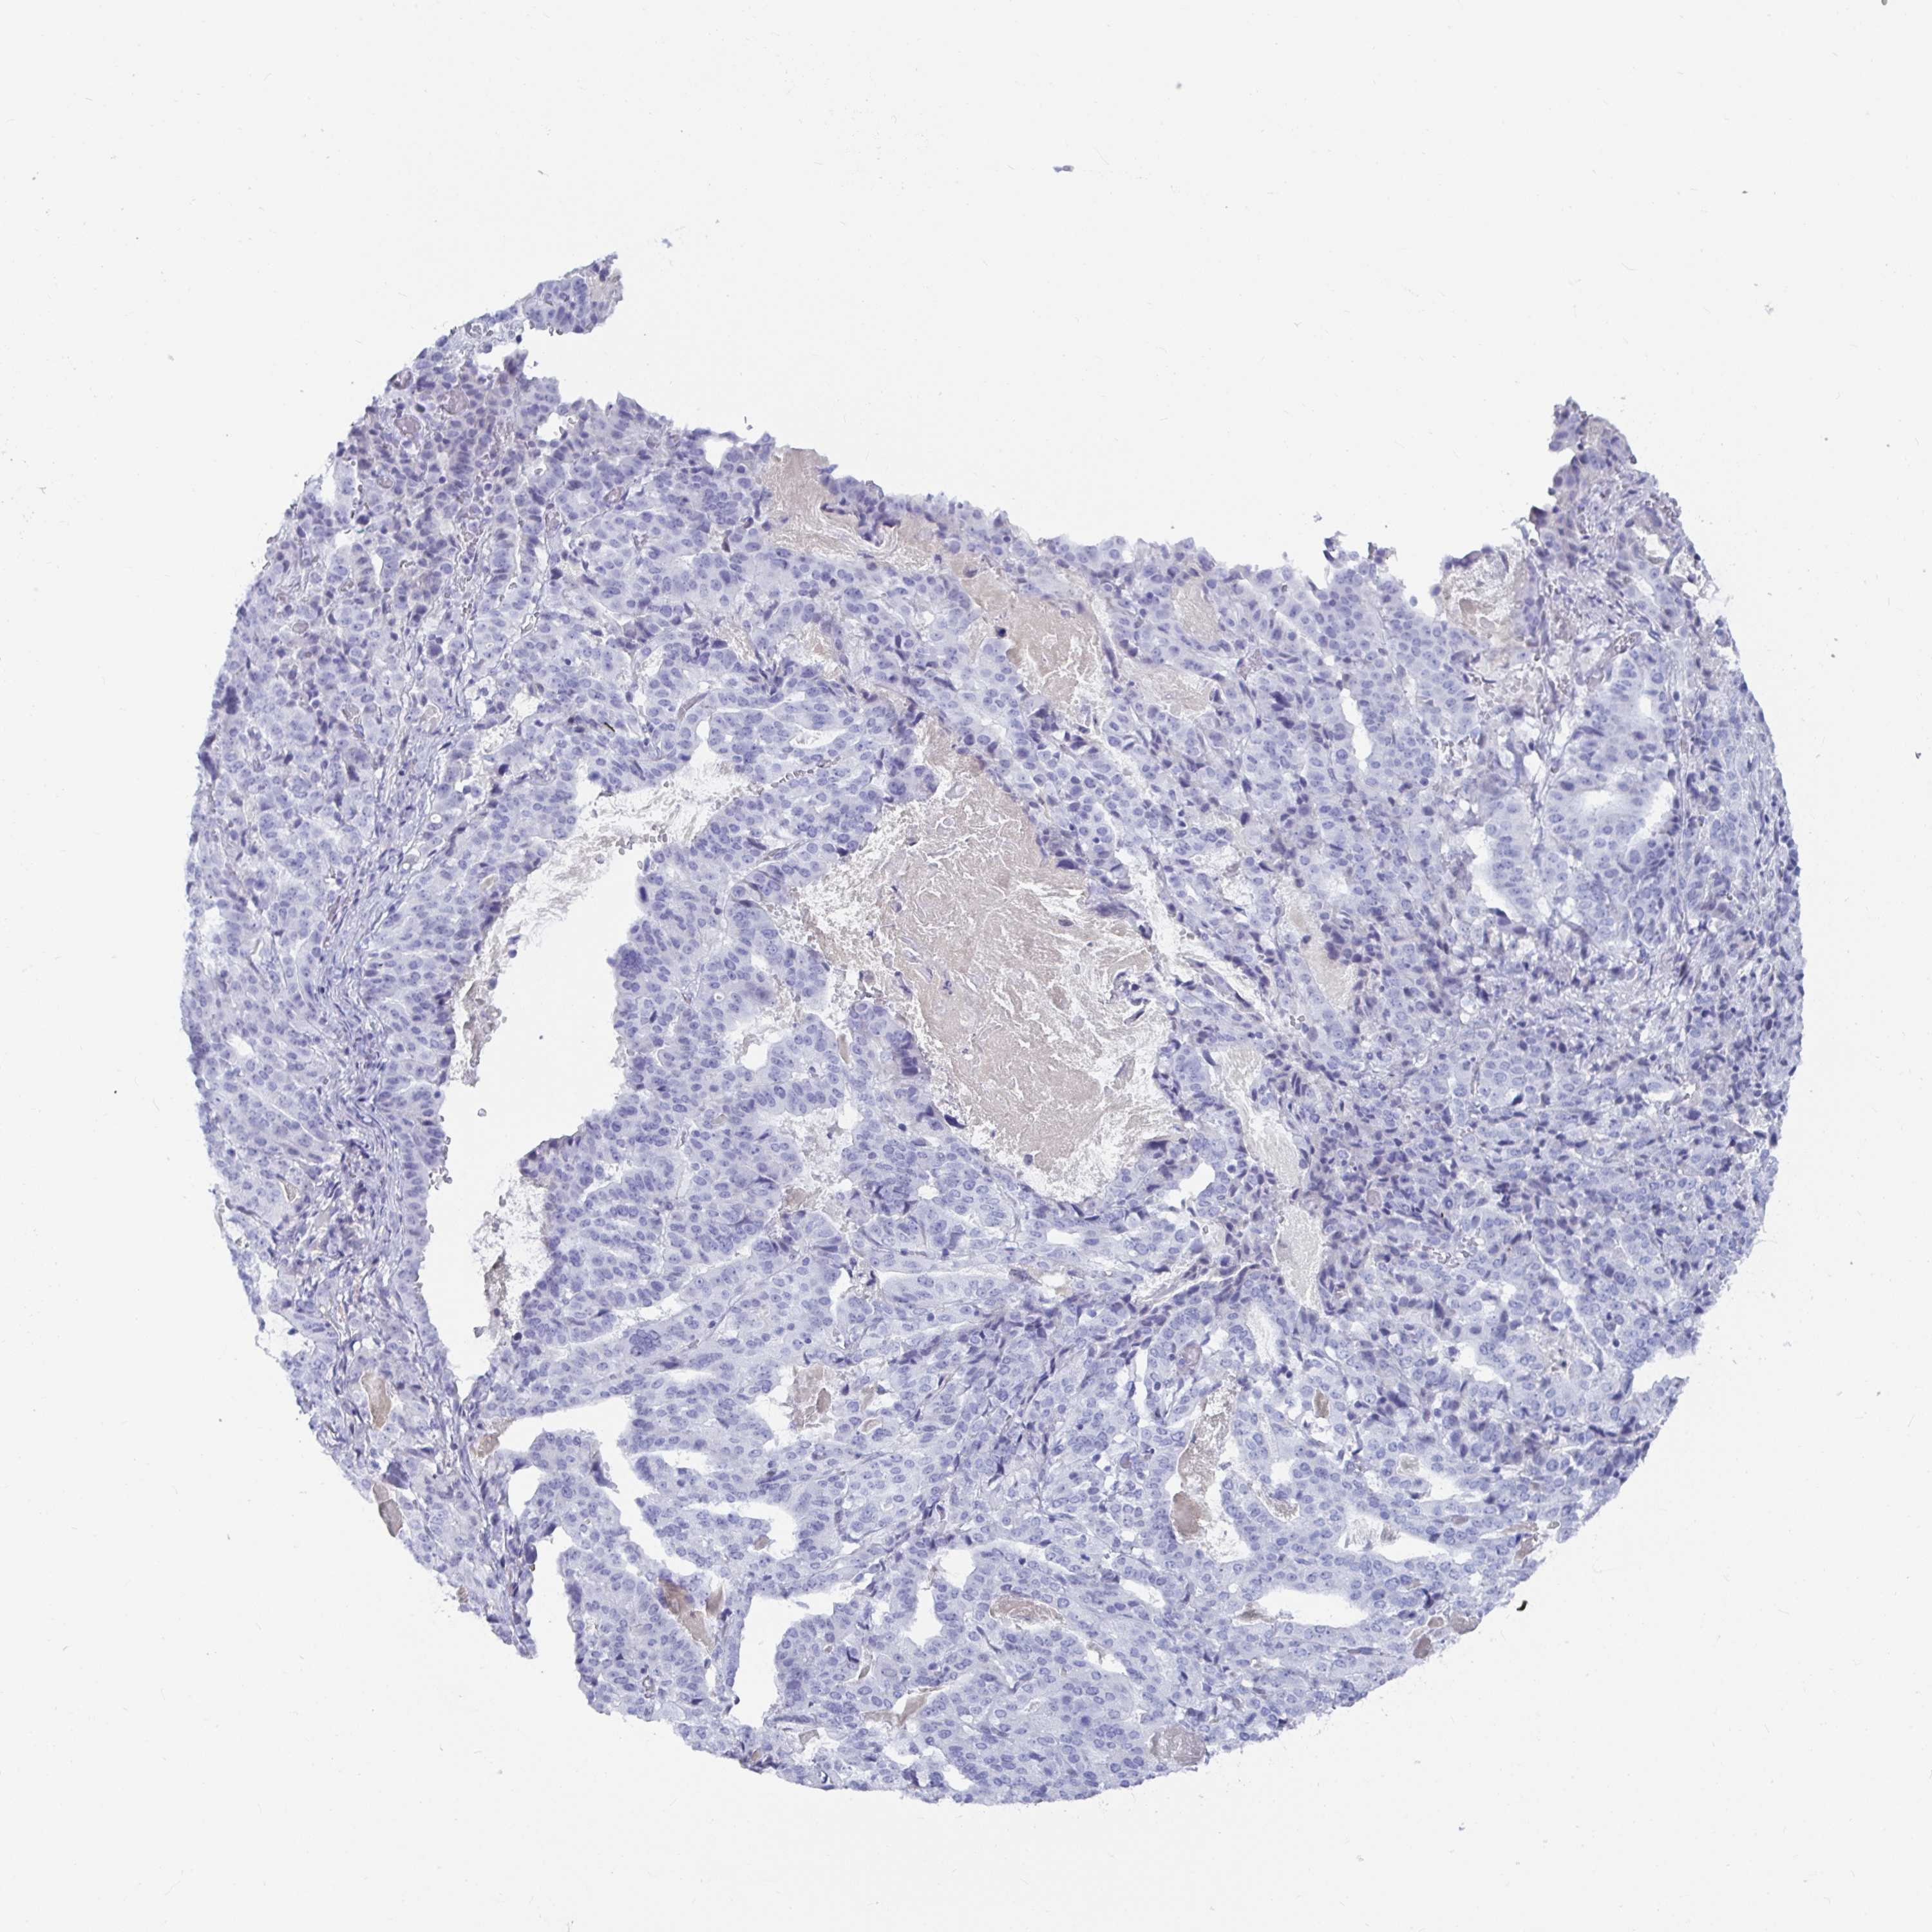

STOMACH CANCER - Protein expressioni

A mouse-over function shows sample information and annotation data. Click on an image to view it in a full screen mode. Samples can be filtered based on level of antibody staining by selecting one or several of the following categories: high, medium, low and not detected. The assay and annotation is described here.

Antibody stainingi

Antibody staining in the annotated cell types in the current human tissue is reported as not detected, low, medium, or high, based on conventional immunohistochemistry profiling in selected tissues. This score is based on the combination of the staining intensity and fraction of stained cells.

Each image is clickable and will lead to virtual microscopy that enables deeper exploration of all samples and also displays staining intensity scores, fraction scores and subcellular localization as well as patient and tissue information for each sample.

Antibody HPA044572

Antibody HPA056798

Antibody CAB016733

Antibody CAB034368

Staining

High

Medium

Low

Not detected

Intensity

Strong

Moderate

Weak

Negative

Quantity

>75%

75%-25%

<25%

None

Location

Nuclear

Cytoplasmic/membranous

Cytoplasmic/membranous,nuclear

Adenocarcinoma, NOS